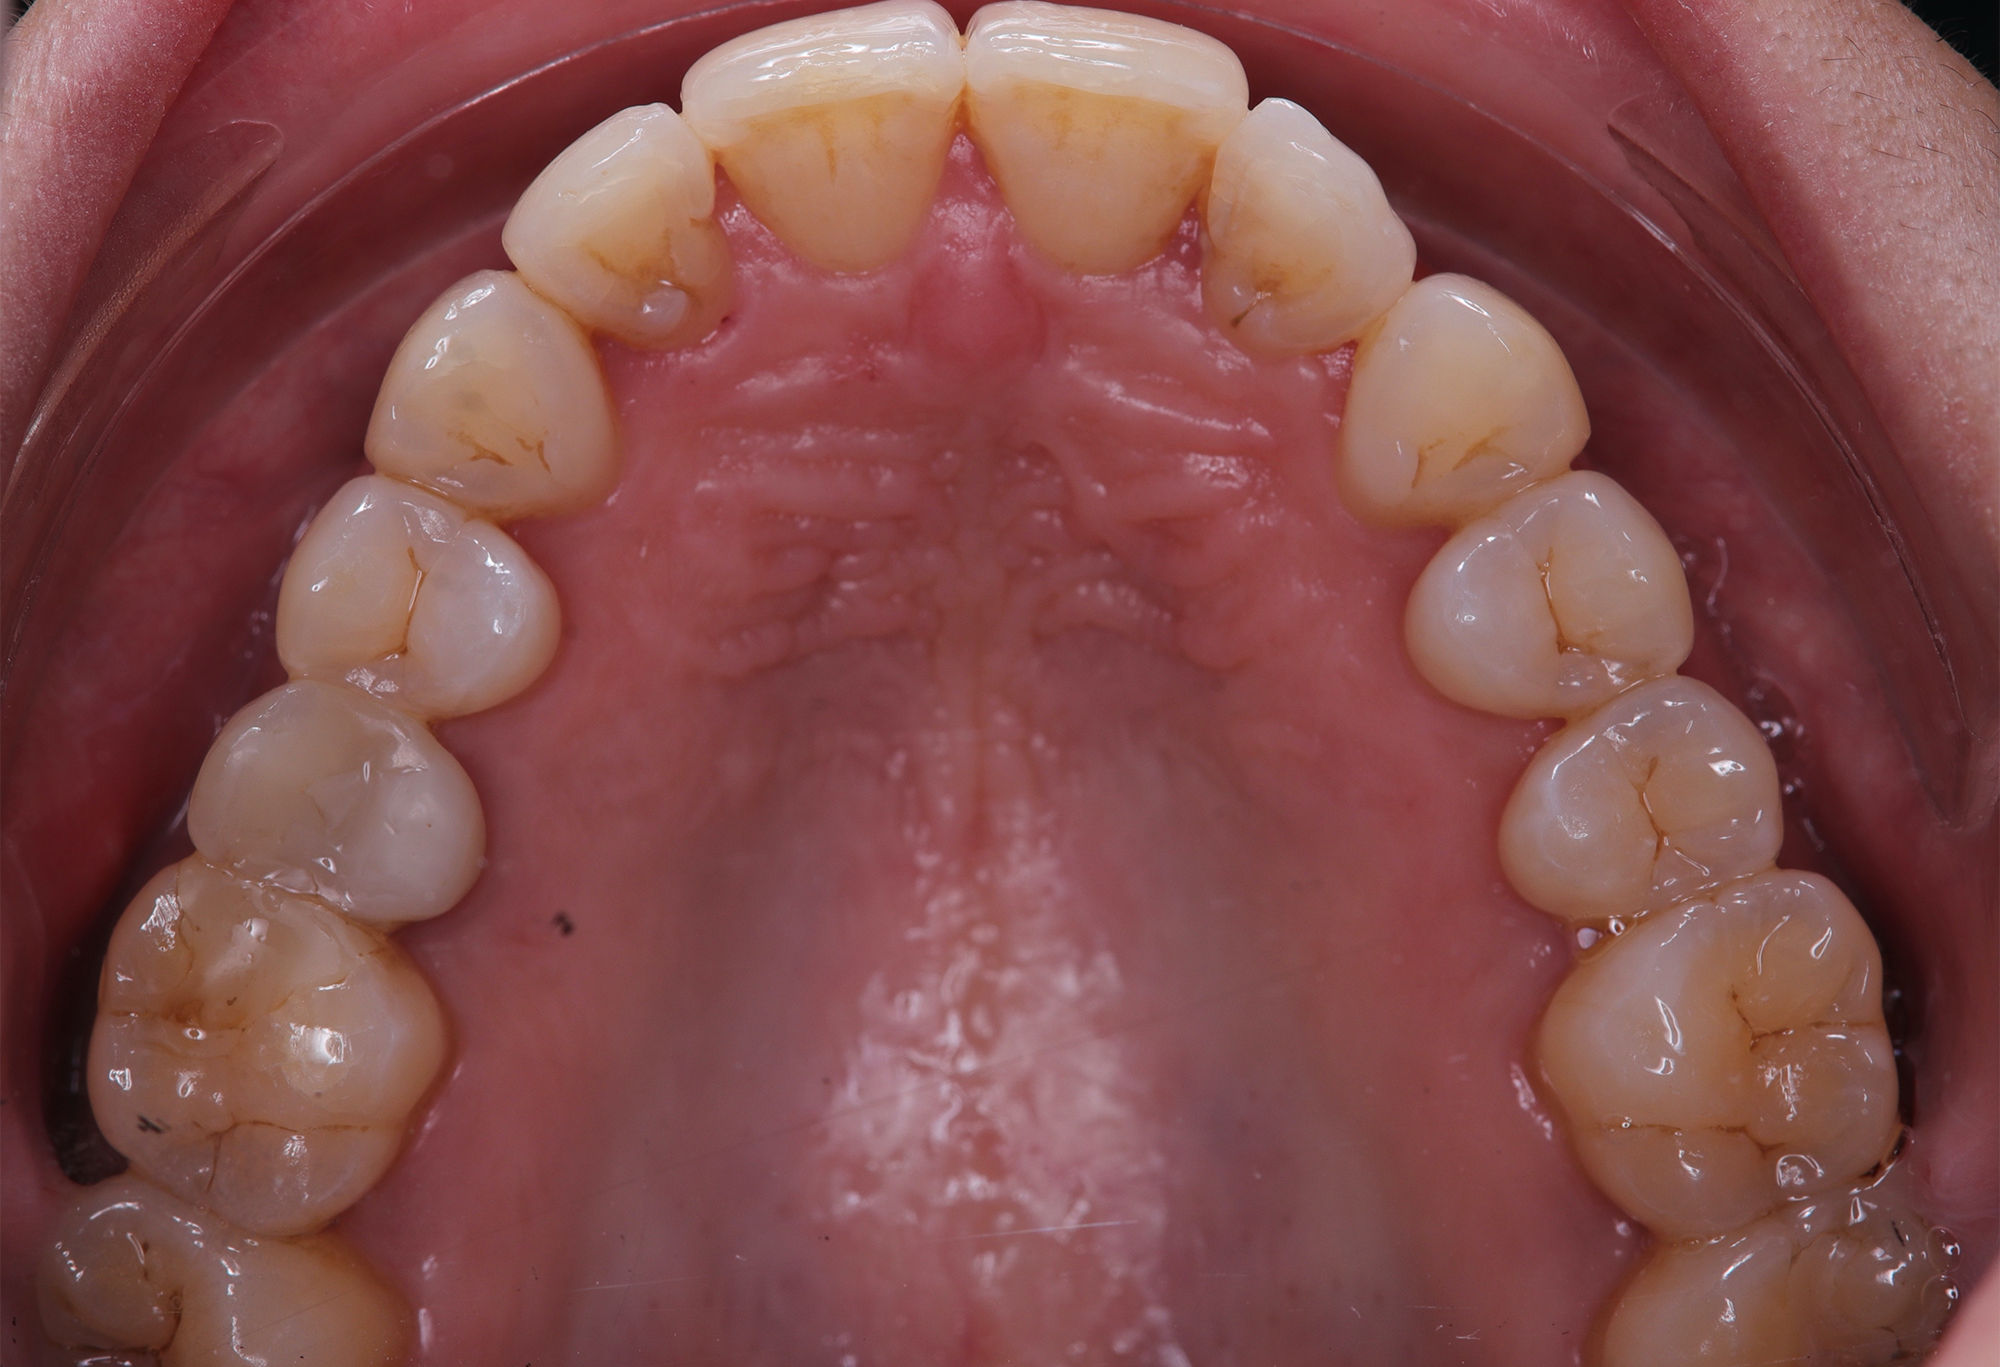

To correct the misalignment and anterior crossbite without compromising tissue stability, a slower orthodontic treatment plan was devised using the Spark Advanced clear aligner system. The initial phase involved 36 aligners designed to gently expand and realign the dental arches, limiting the rate of tooth movement. Strategic interproximal reduction (IPR) was performed in the anterosuperior region (between teeth #21 and #11) to create the necessary space for proper alignment while avoiding excessive loading on the tissues.

To refine the results and enhance aesthetics, a second phase incorporating an additional 17 aligners was introduced. During this refinement stage, careful IPR in the lower arch helped harmonize the midline and achieve a balanced occlusion. Once satisfactory alignment was reached, provisional composite restorations were placed on the upper lateral incisors to aesthetically close any interproximal gaps.

At the conclusion of the treatment, the patient achieved excellent dental alignment and a stable occlusal relationship, particularly in the anterior region. Radiographs and clinical assessments confirmed that there was no further bone loss and that previous improvements were maintained. The aesthetic enhancement from the composite restorations further contributed to the overall success of the treatment.